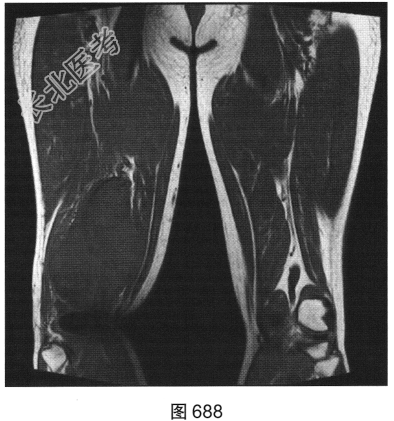

- 多项选择题3.[提示]为进一步明确诊断,患者进一步行CT及MRI检查, 如图686~图691所示。患者CT及MRI的阳性影像表现有( )

A、T2压脂序列上肿块内可见条状高信号

B、右大腿后方肌群内见肿块影

C、T1WI及T2WI均表现为实性肿块,均以等信号为主

D、T2压脂序列呈高信号,周围见明显水肿信号

E、肿块边界较清,密度较均匀

F、肿块周围肌间隙清晰,邻近组织呈受压改变

G、T2WI上可见斑片状稍高信号及低信号分隔